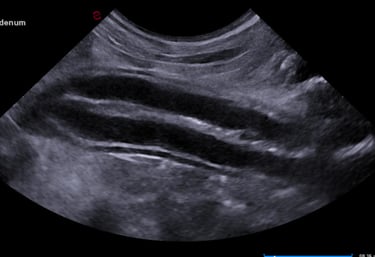

abdominal ultrasound

Complete abdominal ultrasound captures detailed videos and images of internal organs to aid in the diagnosis of various conditions and help guide treatment decisions.

Organs interrogated include liver, gallbladder, pancreas, adrenal glands, kidneys, bladder, spleen, colon, stomach, small intestines, lymph nodes, vessels, +/- reproductive organs.